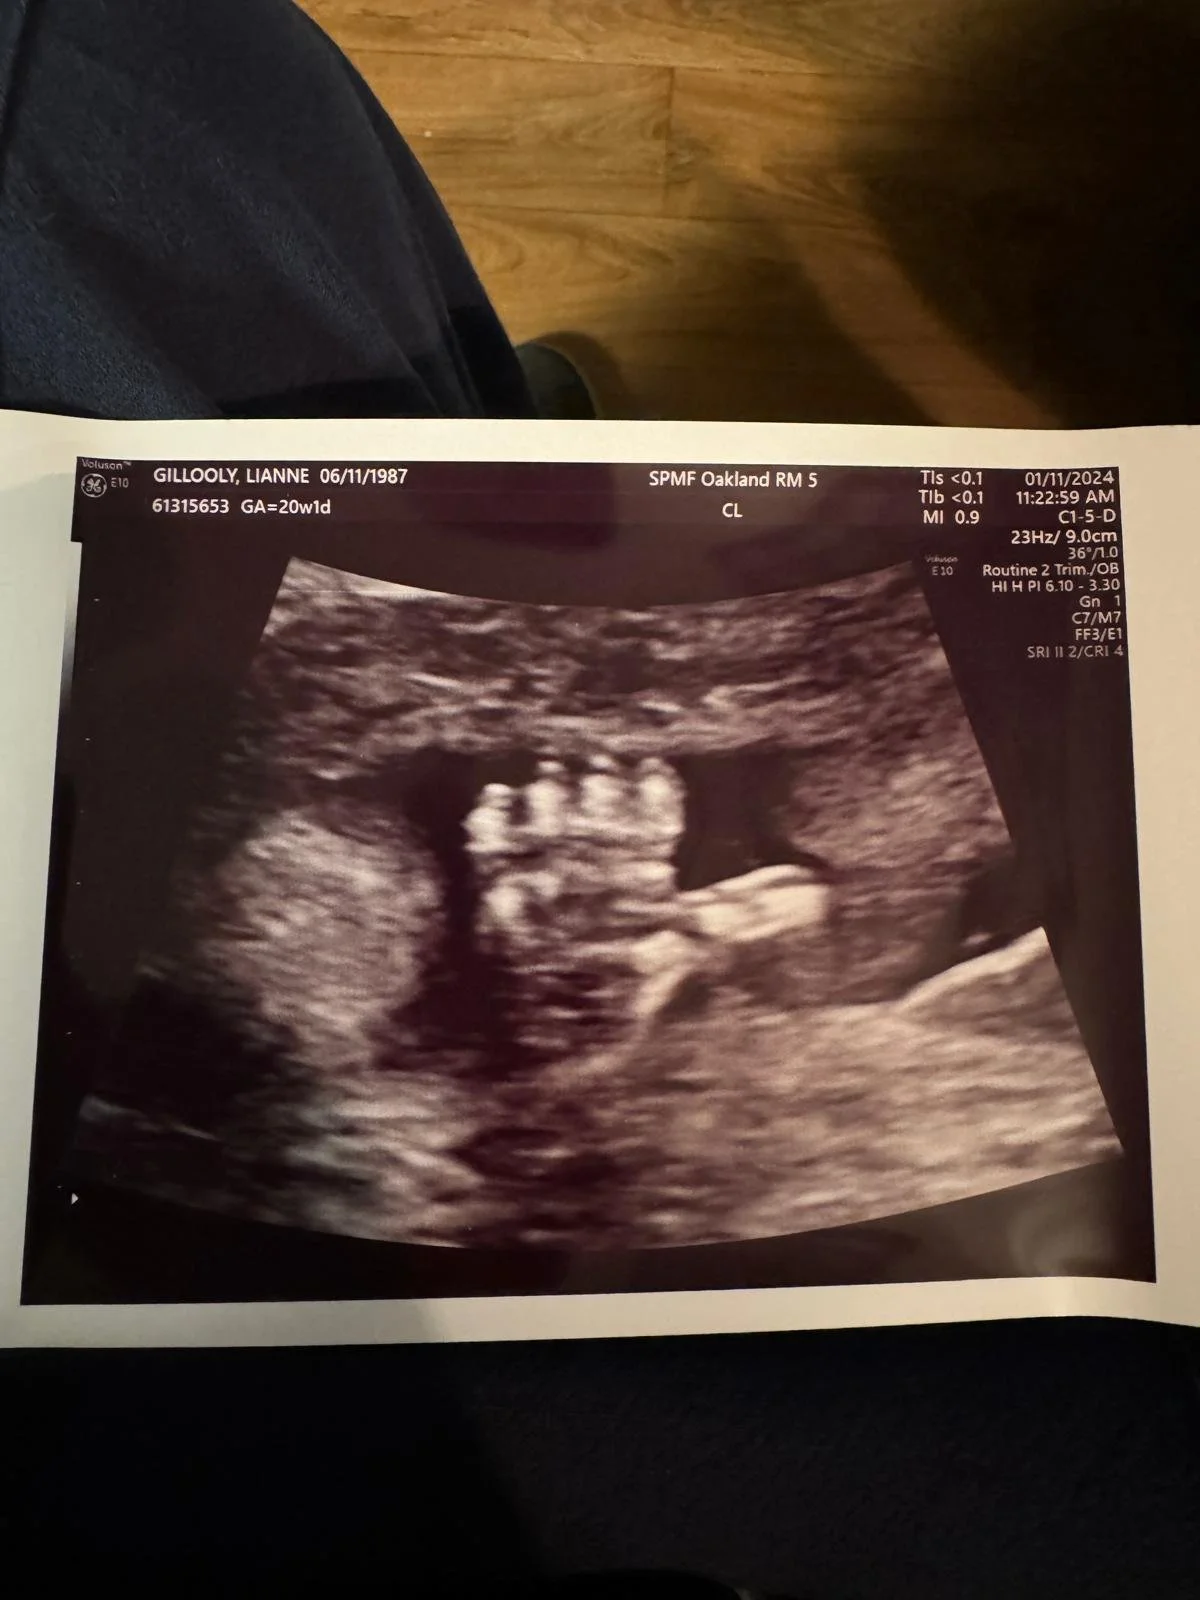

Mike and I showed up to the twenty week scan feeling high on life. Having made it through a difficult first trimester, I was energized and enlivened by how great I felt during the second trimester. Except for a bump on my skin I had gotten checked out, my body felt amazing. I had never felt more grateful to be alive.

The scan took twice as much time as the last one. The technician kept retracing one spot on my belly with the wand. We thought nothing of it. Mike kept me entertained by naming all the body parts as they emerged on the screen. After a while, he dozed off in the chair next to me. The technician printed out photos, including one of our baby giving us a thumbs up.  As we waited for the doctor, Mike wrote a message to send to our families alongside this image.

Guests began to arrive. We wrapped the picture of Cozmo’s sonogram around a vigil candle. My mind was racing. Did we have enough toilet paper? We placed sweetgrass, cedar, and sage on the altar. I noticed that the carpet needed vacuuming. A knitted giraffe rattle and a wooden toy airplane were placed next to a tiny pair of Moroccan slippers, all gifts for Cozmo. We’d asked them to bring food for after. Were there enough plates and forks?